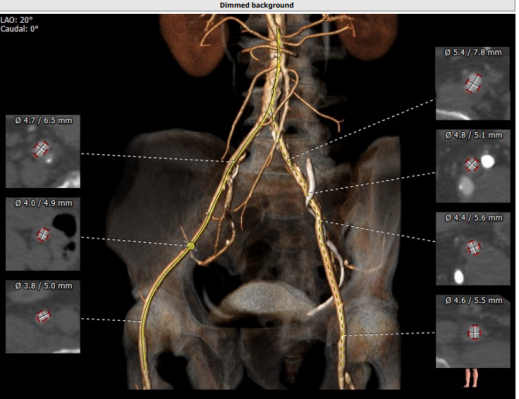

入路情况:左股,主动脉弓部有钙化